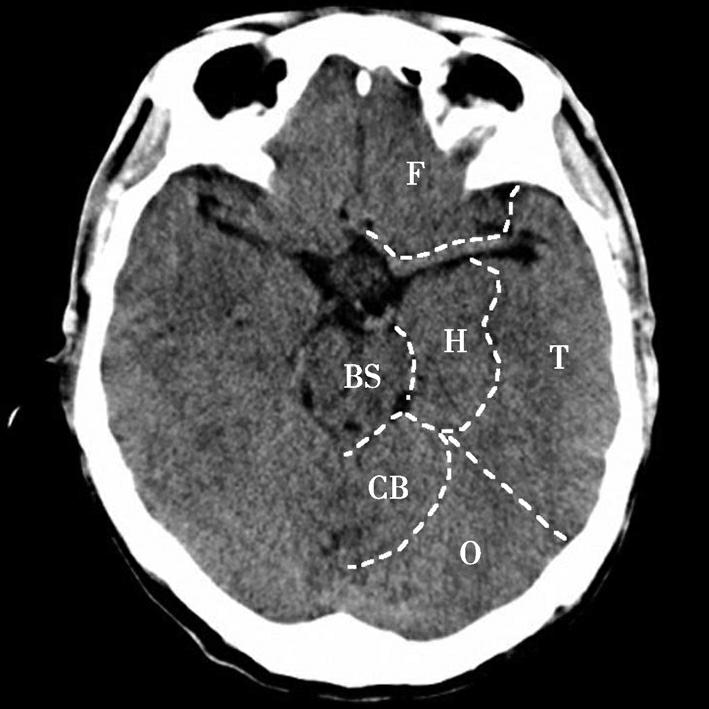

图1-2-17 脑叶划分示意图

CB.小脑;BS.脑干;T.颞叶;F.额叶;O.枕叶;H.海马回及海马结构

鞍上池位于层面的中部,多数呈六角星形,其前角连大脑纵裂池、两个前外侧角通外侧裂池、两个后外侧角延续为环池,后角为中脑双侧大脑脚之间的脚间池。鞍上池的六条边为前面的两侧额叶底部、外侧边为颞叶钩回,后两条边为大脑脚。如后方为脑桥,则鞍上池呈五角星形。鞍上池内前部有视交叉、视束及漏斗,两侧有颈内动脉。乳头体位于鞍上池后部中脑前方。鞍上池两侧为颞叶,颞叶内侧前部为杏仁体,杏仁体后方为海马,海马内后方向内突出的脑回为海马旁回,海马外侧可见侧脑室颞角。在颞叶前方通过外侧裂池与额叶相隔。鞍上池后方为中脑、中脑后部的中脑导水管及中脑两侧的环池。

鞍上池是该层面需要重点观察的部位。其形态及密度的改变均提示病变(图1-2-18、图1-2-19),例如鞍上池失去正常五角星或六角星形态、甚至闭塞,或者鞍上池密度升高或不均匀。此外,环池闭塞多见于颅内压严重增高的患者,为诊断脑疝的影像学依据(图1-2-20)。